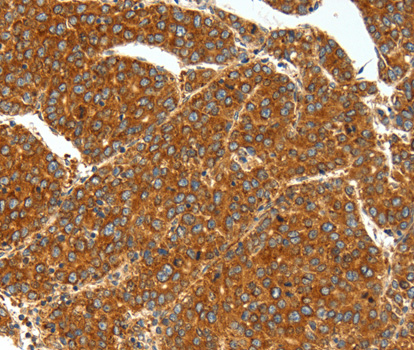

• A3134: image 2

Immunohistochemistry of paraffin-embedded human liver cancer tissue using SSTR1 antibody.